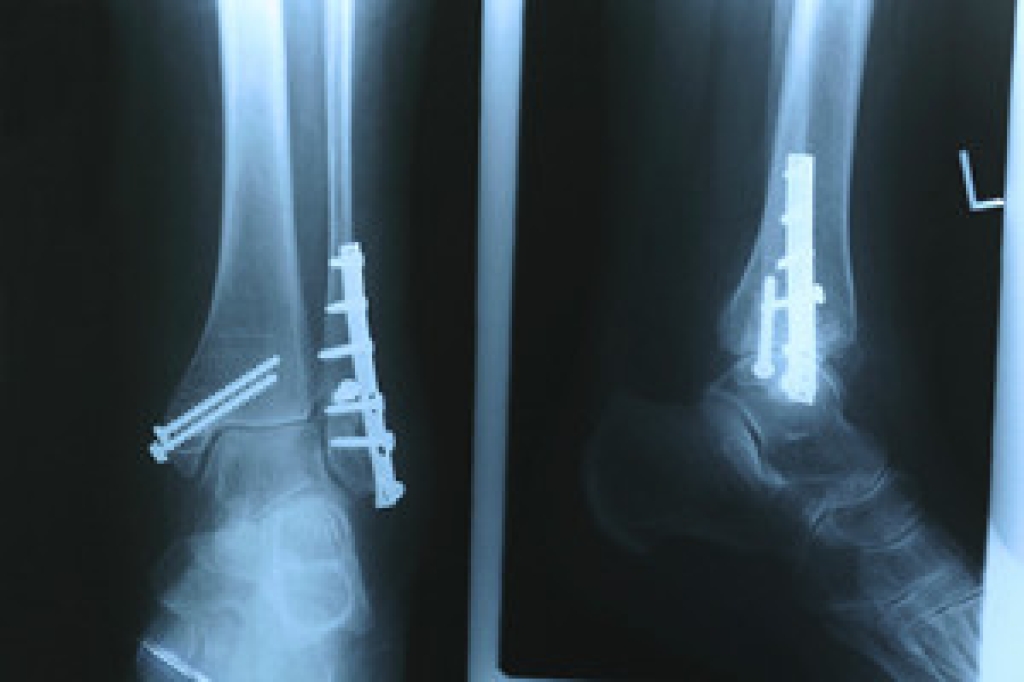

Understanding the Basics of Stress Fractures

Stress fractures primarily occur when the feet are overused. As foot muscles get tired, they are unable to absorb as much shock from impact, and the stress is transferred to the bone. Over half of all stress fractures occur in the lower leg, and athletes involved in activities such as basketball, running, and gymnastics are at a higher risk for trauma. Since stress fractures can be difficult to diagnose through an X-Ray, communicating the risk of stress fractures to doctors is key, because they may have to resort to CT scans or MRIs. If diagnosed with a stress factor, rest is key.  However, a podiatrist may be able to recommend shoe inserts or braces to help as well. For the best treatment methods, please consult with your local podiatrist.

Dealing with Stress Fractures of the Foot and Ankle

Stress fractures occur in the foot and ankle when muscles in these areas weaken from too much or too little use.  The feet and ankles then lose support when walking or running from the impact of the ground. Since there is no protection, the bones receive the full impact of each step. Stress on the feet can cause cracks to form in the bones, thus creating stress fractures.

Pain from the fractures occur in the area of the fractures and can be constant or intermittent. It will often cause sharp or dull pain with swelling and tenderness. Engaging in any kind of activity which involves high impact will aggravate pain.